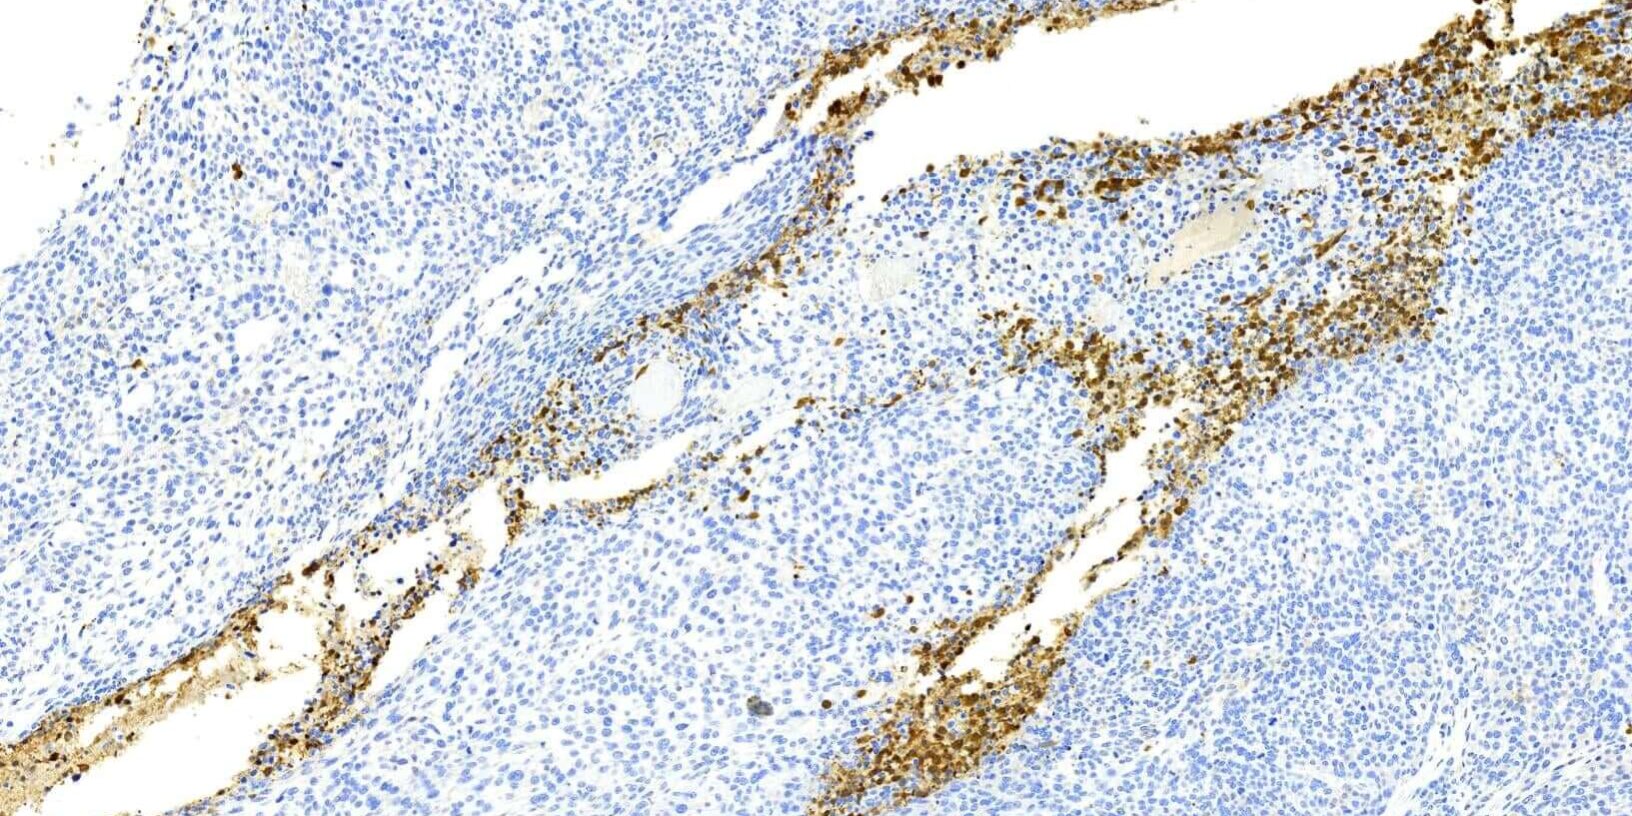

Caspase 級聯反應 (caspase cascade)是細胞凋亡早期的重要細胞反應,其中 caspase3 在凋亡訊號傳導的許多途徑中都有重要的作用。Casepase蛋白酶除了參與核酸的剪切外,也與核纖肽(在細胞膜上)和肌動蛋白(actic, 細胞骨架的成分)的分解過程有關。也因此,Caspase 3的表現與TUNEL assay不同,Caspase 3的陽性訊號可能出現在細胞膜、細胞質及細胞核,但TUNEL僅表現於細胞核。

相較於TUNEL assay,Caspase 3表現可同時出現於細胞膜、細胞質及細胞核,如何避免染色出現過多背景雜訊,考驗實驗室的專業能力!!